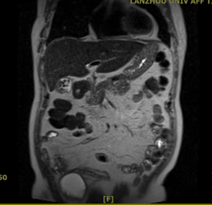

近日,兰州石化总医院(甘肃中医药大学第四附属医院)普外科团队成功为一名78岁男性患者实施腹腔镜下胆囊切除术+3mm超细胆道镜下经胆囊管胆总管探查取石+一期缝合术。该患者因反复发作胆源性胰腺炎多次住院,此次术前影像学(腹部MR)提示胆囊多发结石,胆总管并未发现明显结石影,经科室讨论后决定术中行经胆囊管胆总管探查。